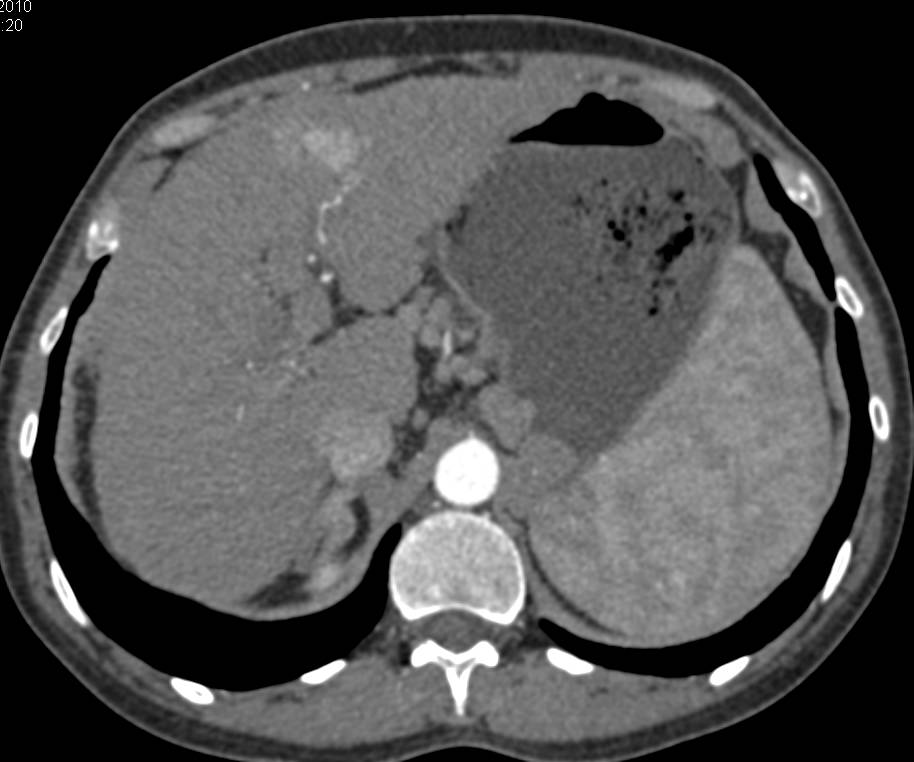

Cholangiocarcinoma